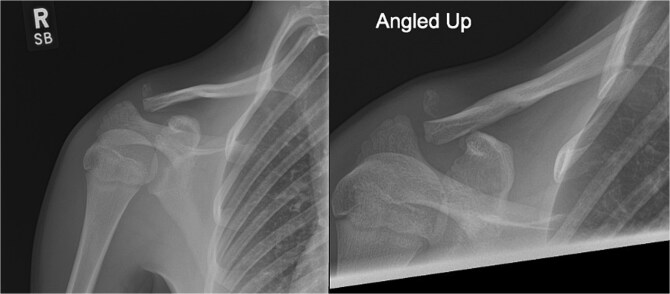

Lateral end clavicle fractures, especially those that are displaced, have a high rate of delayed and non-union. This case series presents three patients with unstable lateral end clavicle fractures successfully treated with TightRope fixation as the sole method of stabilization, demonstrating excellent functional outcomes and minimal complications. The comprehensive literature review reveals mounting evidence with eight reported studies supporting TightRope as an effective standalone treatment option, with the largest published series showing 79% union rates and only 10% complication rates. These findings, combined with the theoretical advantages of avoiding routine hardware removal, lower costs, and compatibility with day-surgery protocols, suggest that TightRope fixation merits serious consideration as a primary treatment modality for appropriately selected patients with lateral end clavicle fractures.

Abstract Image